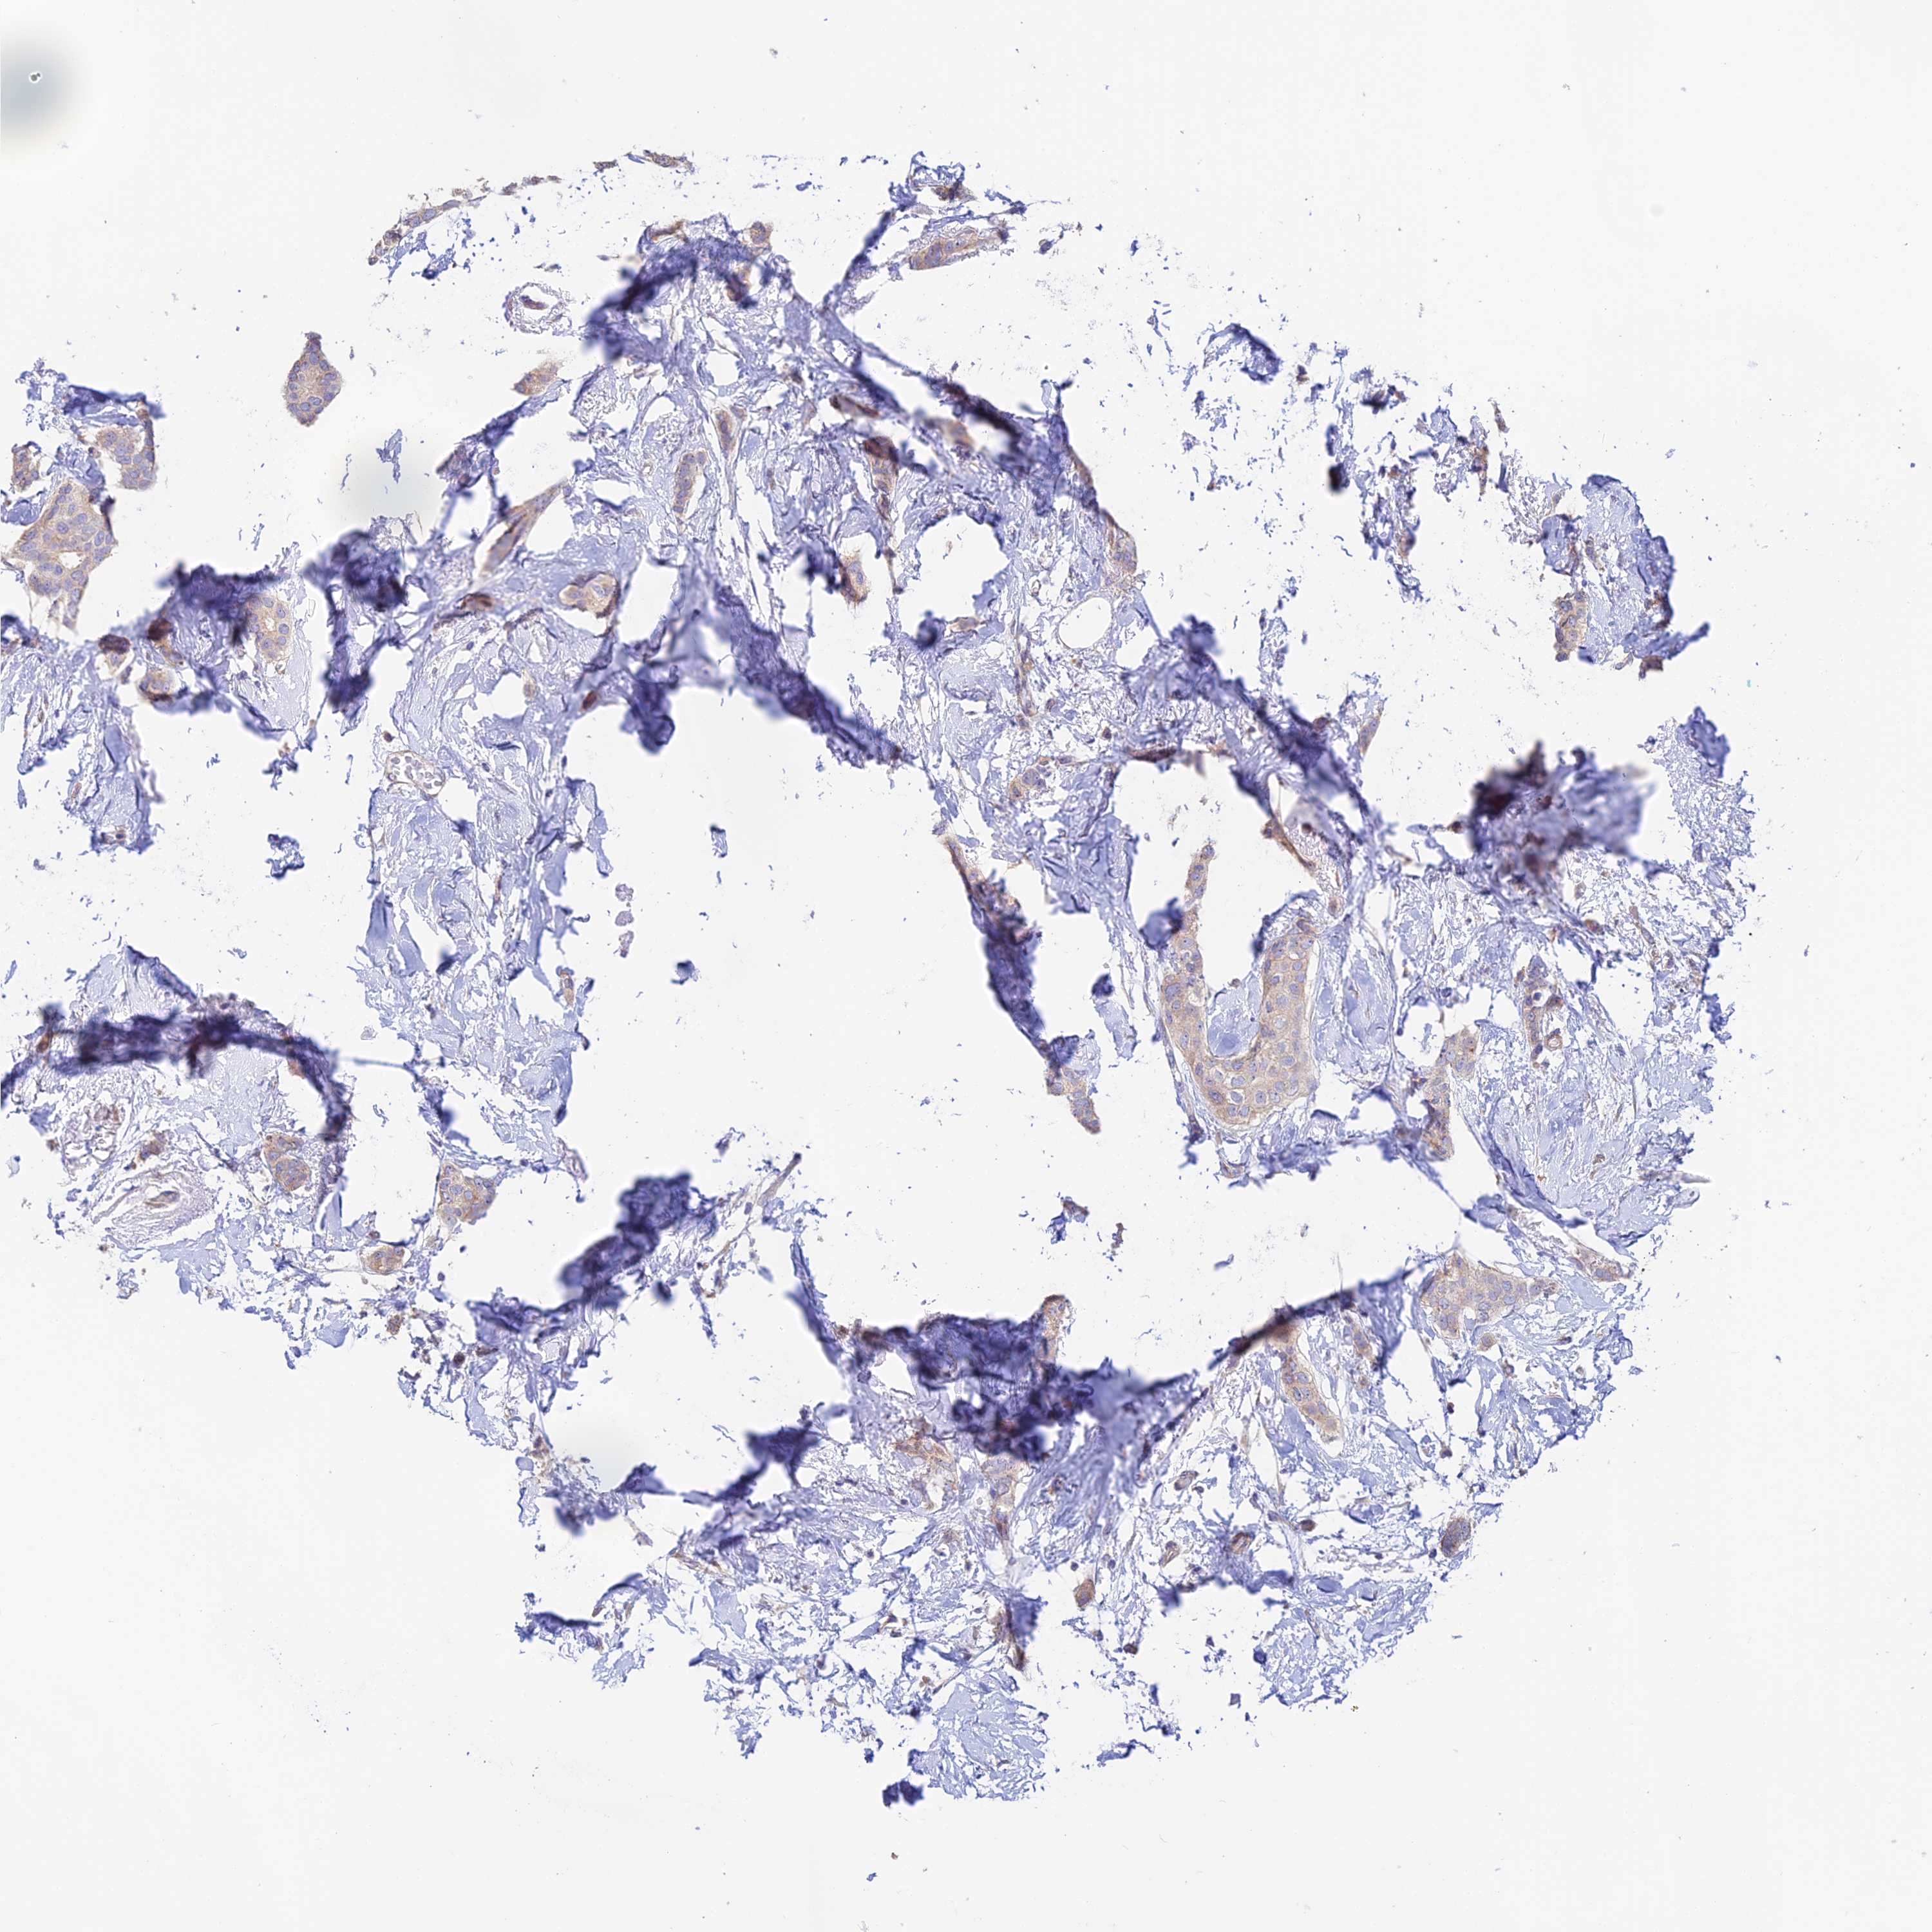

CANCER BREAST CANCER Show tissue menu

BRCA TCGA BRCA VALIDATION PROTEIN EXPRESSION